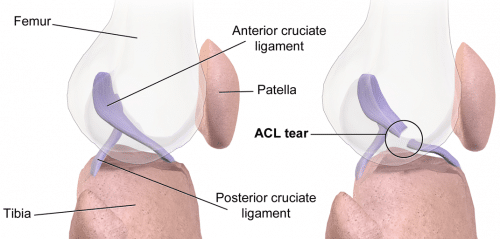

The ACL is an important stabiliser of the knee joint, being the primary restraint to limit anterior translation of the tibia (relative to the femur) and also contributing to knee rotational stability (particularly internal). Consequently, a tear of this important ligament often results in significant functional impairment of the joint.

A plain film radiograph of the knee (AP and lateral) should be taken to exclude bony injuries, any joint effusion, or a lipohaemarthrosis present. A Segond fracture (bony avulsion of the lateral proximal tibia) is pathognomic of ACL injury.

An MRI scan of the knee is gold-standard to confirm the diagnosis (>90% sensitivity), also picking up any associated meniscal tears*